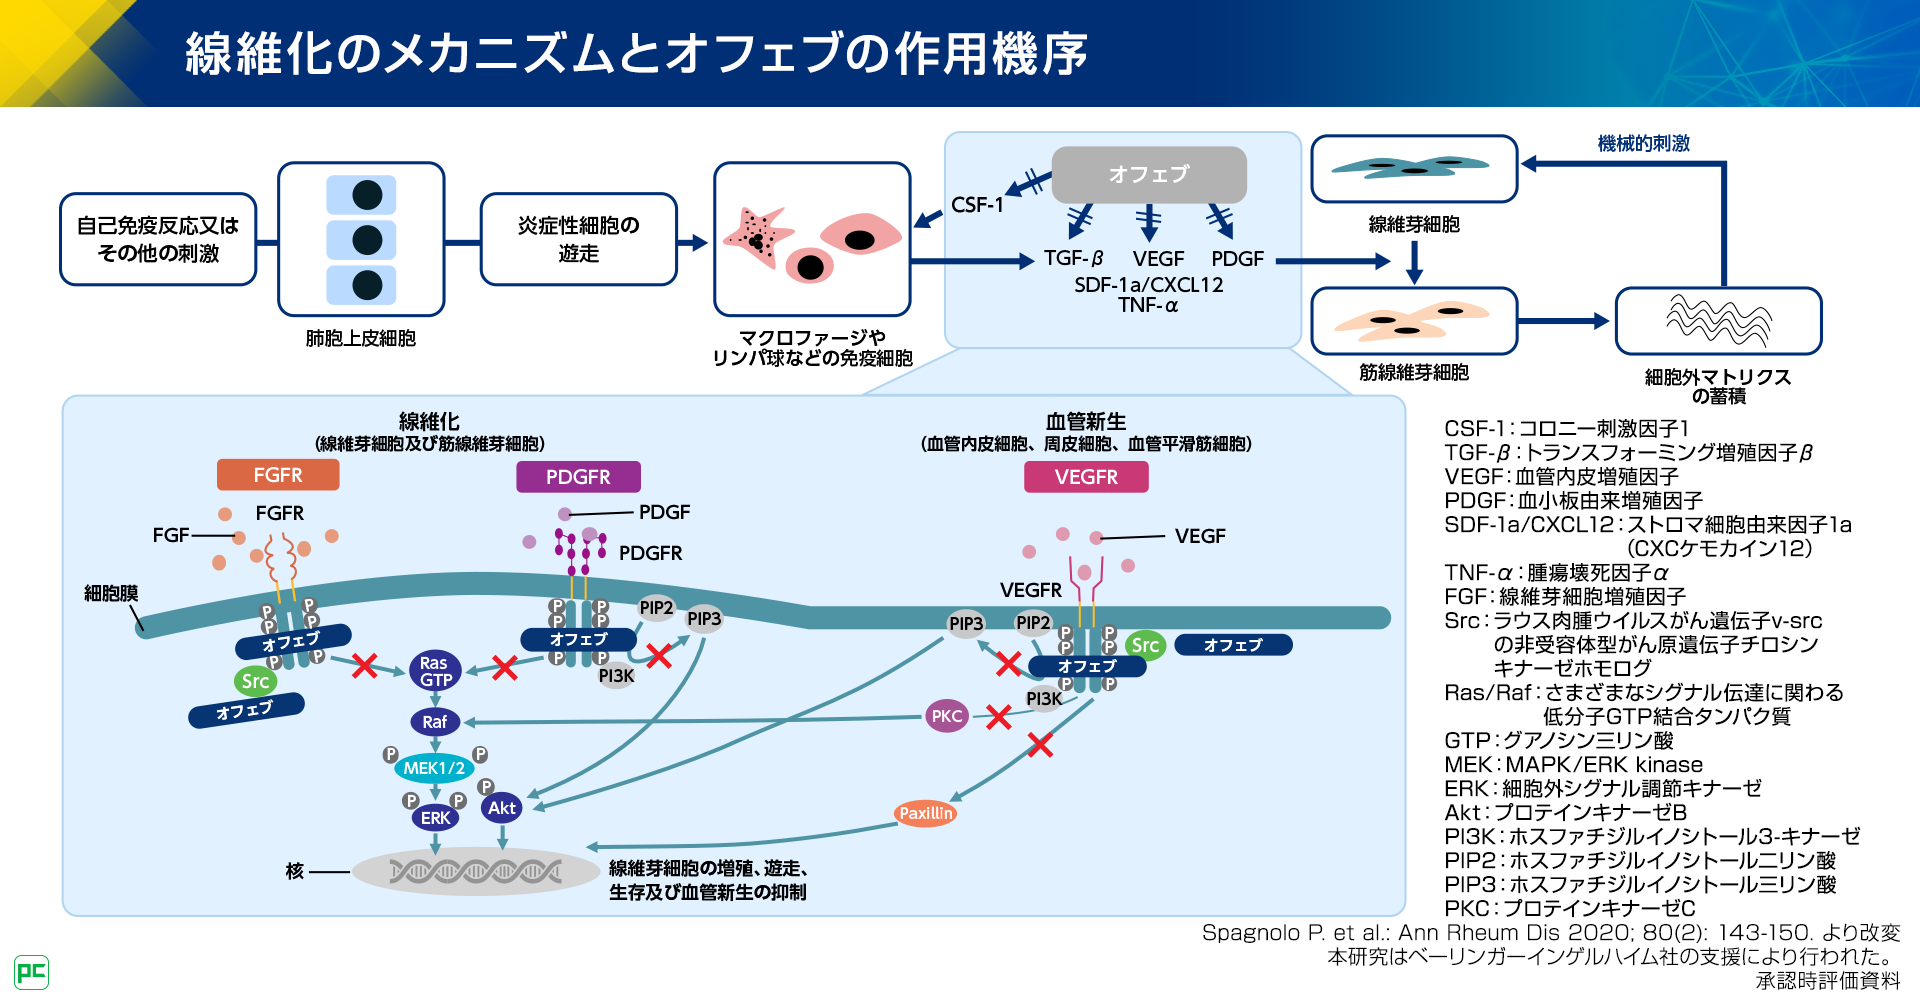

医療法人 心葉消化器外科|トップページ, 進行性線維化を伴うCTD-ILD診療における急性増悪予防の重要性,

進行性線維化を伴うCTD-ILD診療における急性増悪予防の重要性, 論文紹介 | 滋賀医科大学 病理学講座 疾患制御病態学部門,

第52回日本核医学会学術総会/第32回日本核医学技術学会総会学術, 進行性線維化を伴うCTD-ILD診療における急性増悪予防の重要性,

進行性線維化を伴うCTD-ILD診療における急性増悪予防の重要性,